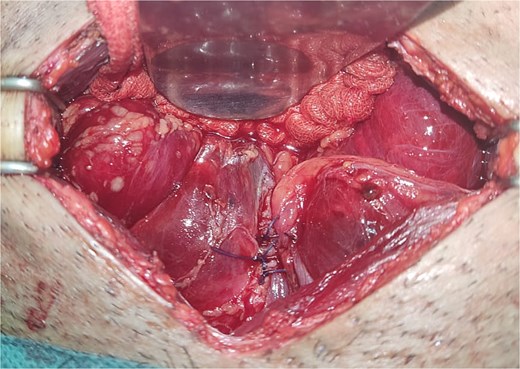

All seven cases of bladder rupture both spontaneous and traumatic were treated surgically via exploratory laparotomy to repair the injury (see Fig. 2). In both types of cases, the ruptured bladder was successfully closed (see Fig. 3). Postoperatively, Redon drain was removed on the second day, and a urinary catheter was maintained for 3 weeks to aid healing.

The image shows an extraperitoneal bladder rupture, revealing a tear in the bladder wall and damage to surrounding tissues.

The image depicts the bladder after surgical repair, showing the successfully sutured rupture site and restored continuity.